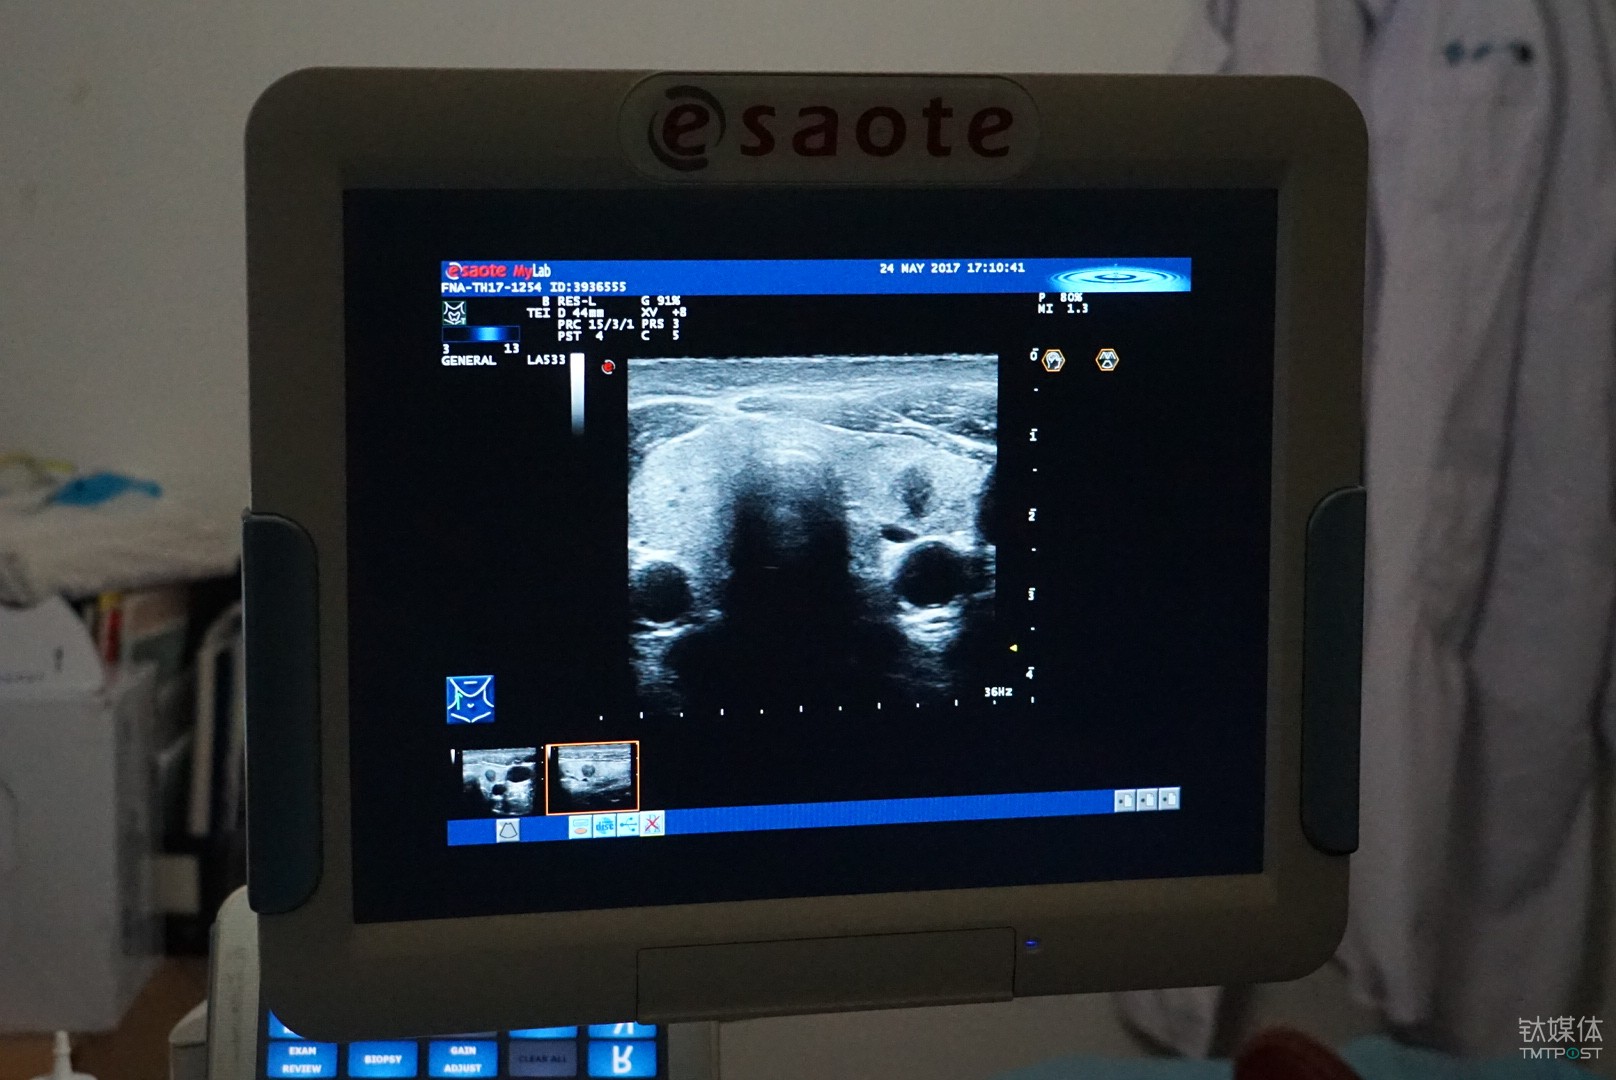

類似的案例也出現在了浙江大學附屬第一學院的超聲醫學科,該病院是率先嘗試用人工智能方式輔助診斷甲狀腺結節的醫學機構。

具體而言,這是一套由德尚韻興與浙江大學特聘教授孔德興團隊主導,依托英特爾至強融合處理器平臺開發而來的輔助診斷系統。

從功能上來說,這是一套基于超聲波影象的甲狀腺結節良惡性的輔助診斷系統,按照甲狀腺結節檢查時候拍攝的醫學影像的特征,通過對圖像的識別和標注,來幫手醫生更準確的做出診斷結論。

對于甲狀腺結節的檢查目前主要依靠超聲的方式,相較于CT和核磁,超聲的好處是自制、靈活、無副作用,所以它也是目前臨床醫學使用最為廣泛的一種檢測手段,不足之處是圖像不清楚、造影比較大,它對醫生的要求就比較高。

按照德尚韻興總經理胡海蓉提供的,“目前三甲病院醫生的平均準確率為60%-70%,基層病院會更加低一些,而輔助診斷系統目前準確率可以達到85%以上,不過由于在我國人工智能還沒有行醫資格,所以我們將其定位為輔助診療,只是給醫生提供一些參考。”